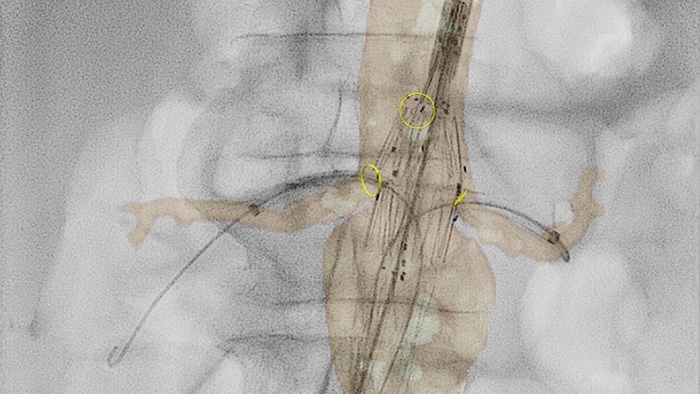

VesselNavigator allows reuse of 3D vascular anatomical information from existing CTA and MRA datasets as a 3D roadmap overlay on a live X-ray image. With its excellent visualisation, VesselNavigator provides an intuitive and continuous 3D roadmap to guide you through vasculature.